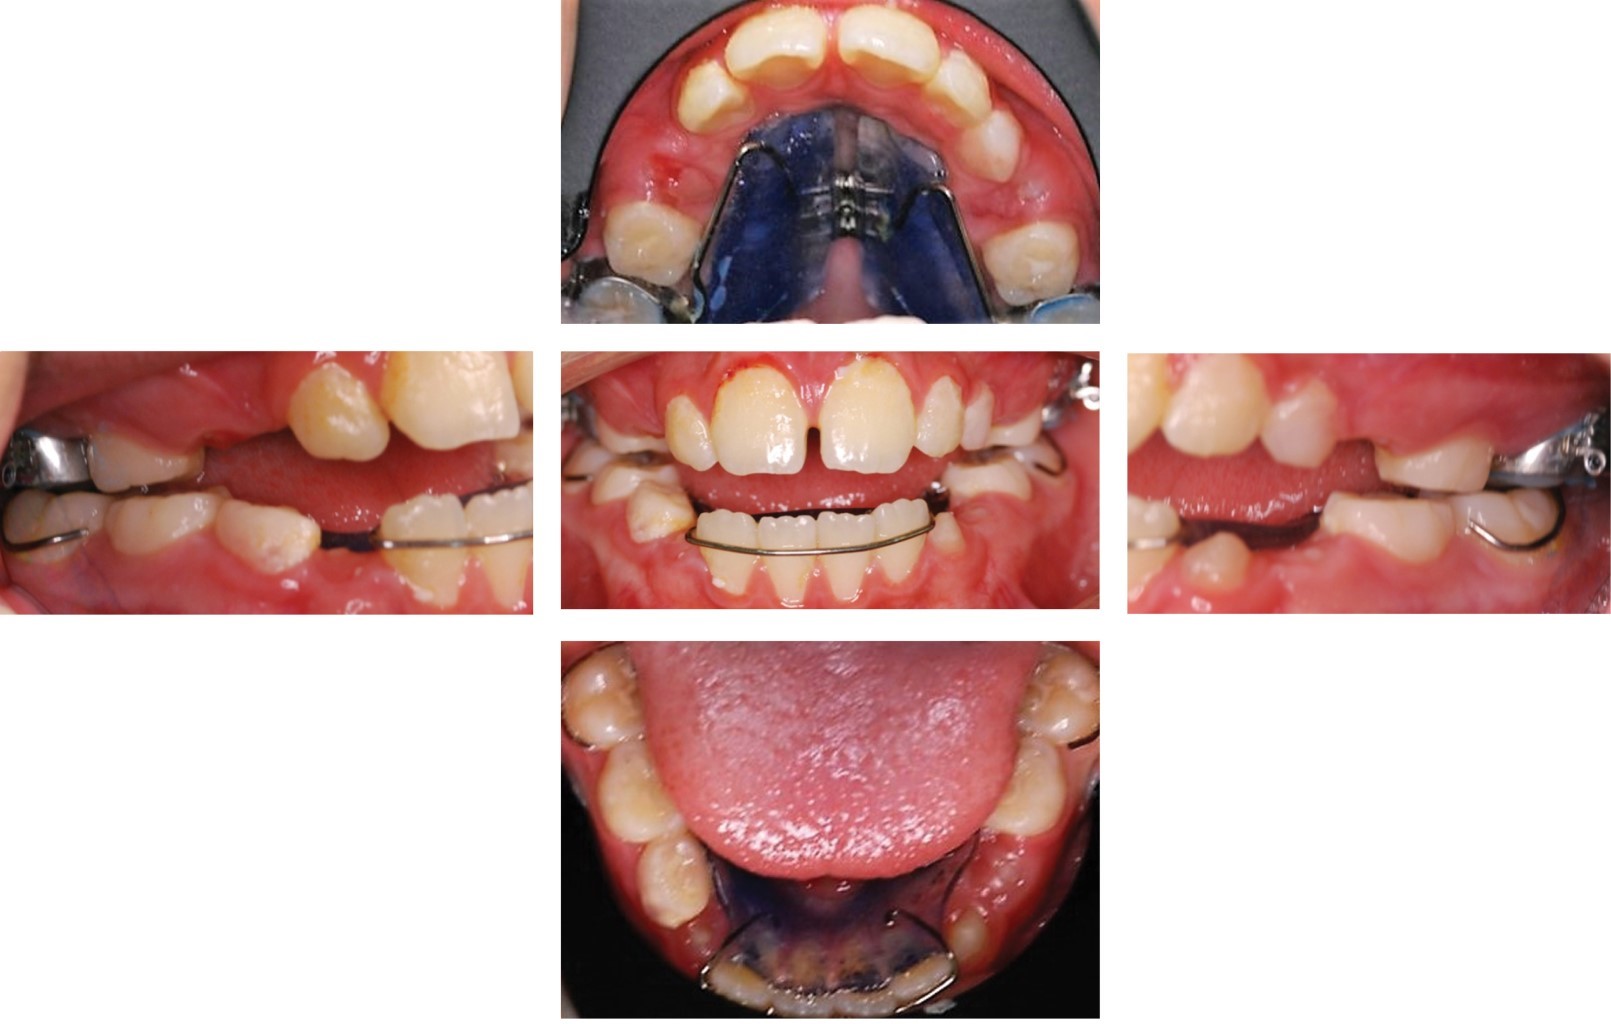

Se inició el tratamiento con la cementación del Hass y arco lingual como se muestra en la Figura 4, se decidió retirar Hass durante dos semanas, debido a que el paciente presentó una tumefacción en zona de tornillo expansor. Se continuó con su uso durante dos semanas más y a los cuatro meses se retiró Hass y se colocó arco palatino con espolones para controlar la proyección lingual (Figura 5).

Figura 4

Figura 5